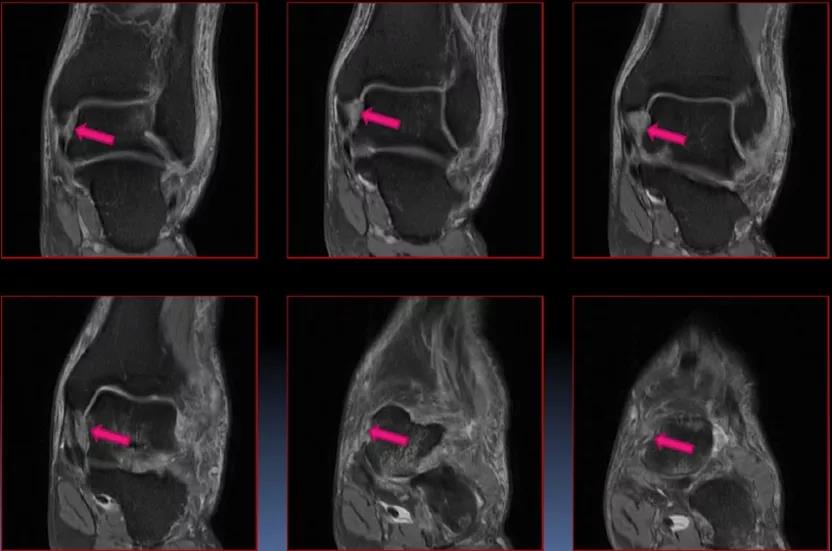

MRI:

三角韧带撕裂